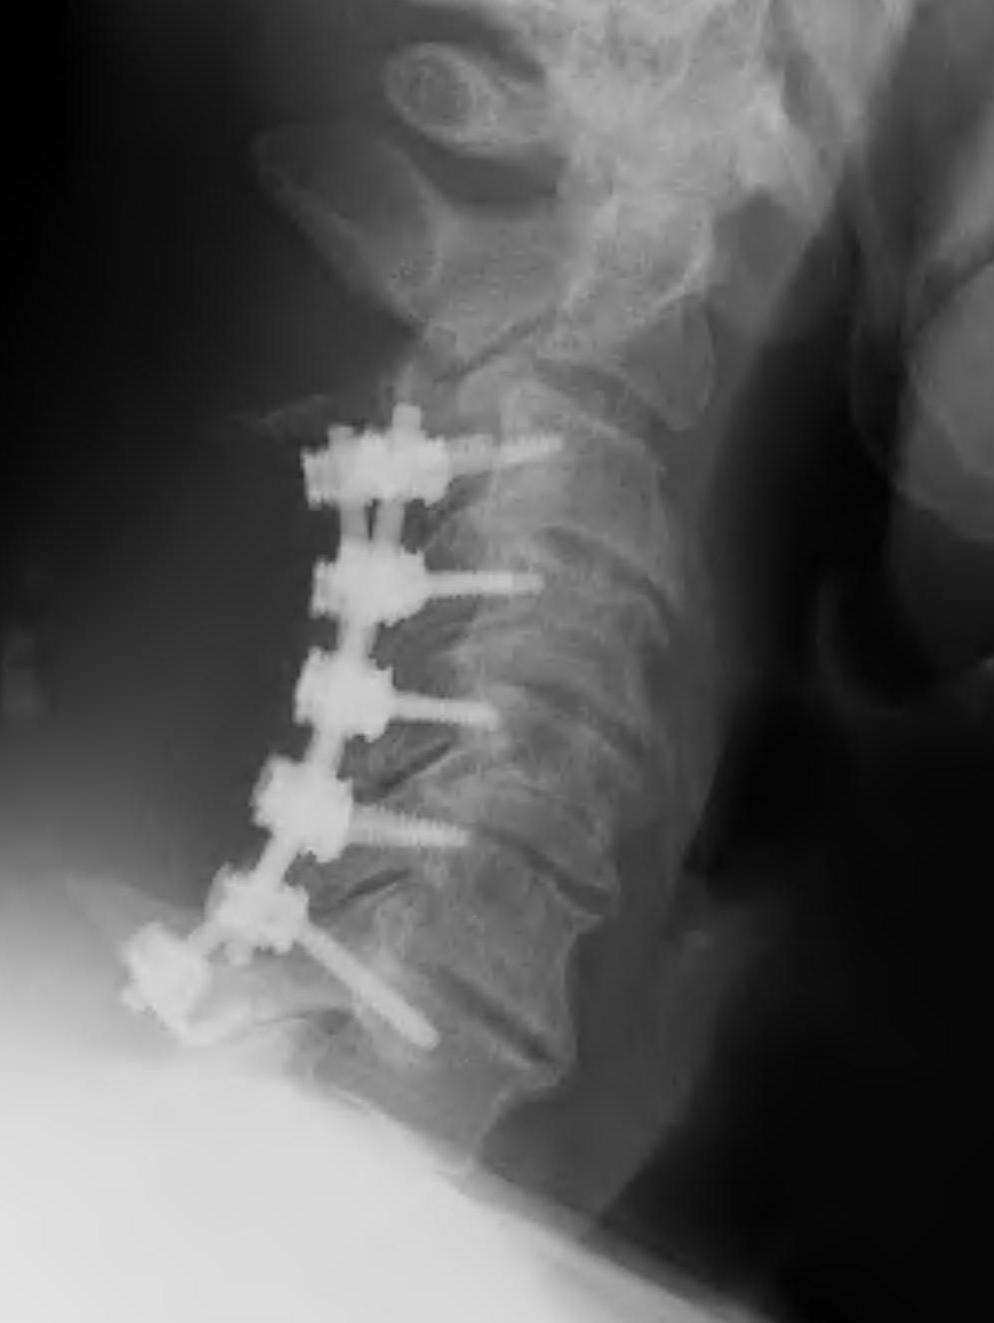

ACDF

Indication

Anterior cord compression

Single or double level compression

Kyphotic deformity

Advantages

Removes entire disc

Maintain / restore lordosis

Disadvantages

Difficulty decompressing the nerve roots in foramen

Difficult to decompression vertebral bodies

Relatively contra-indicated with OPLL